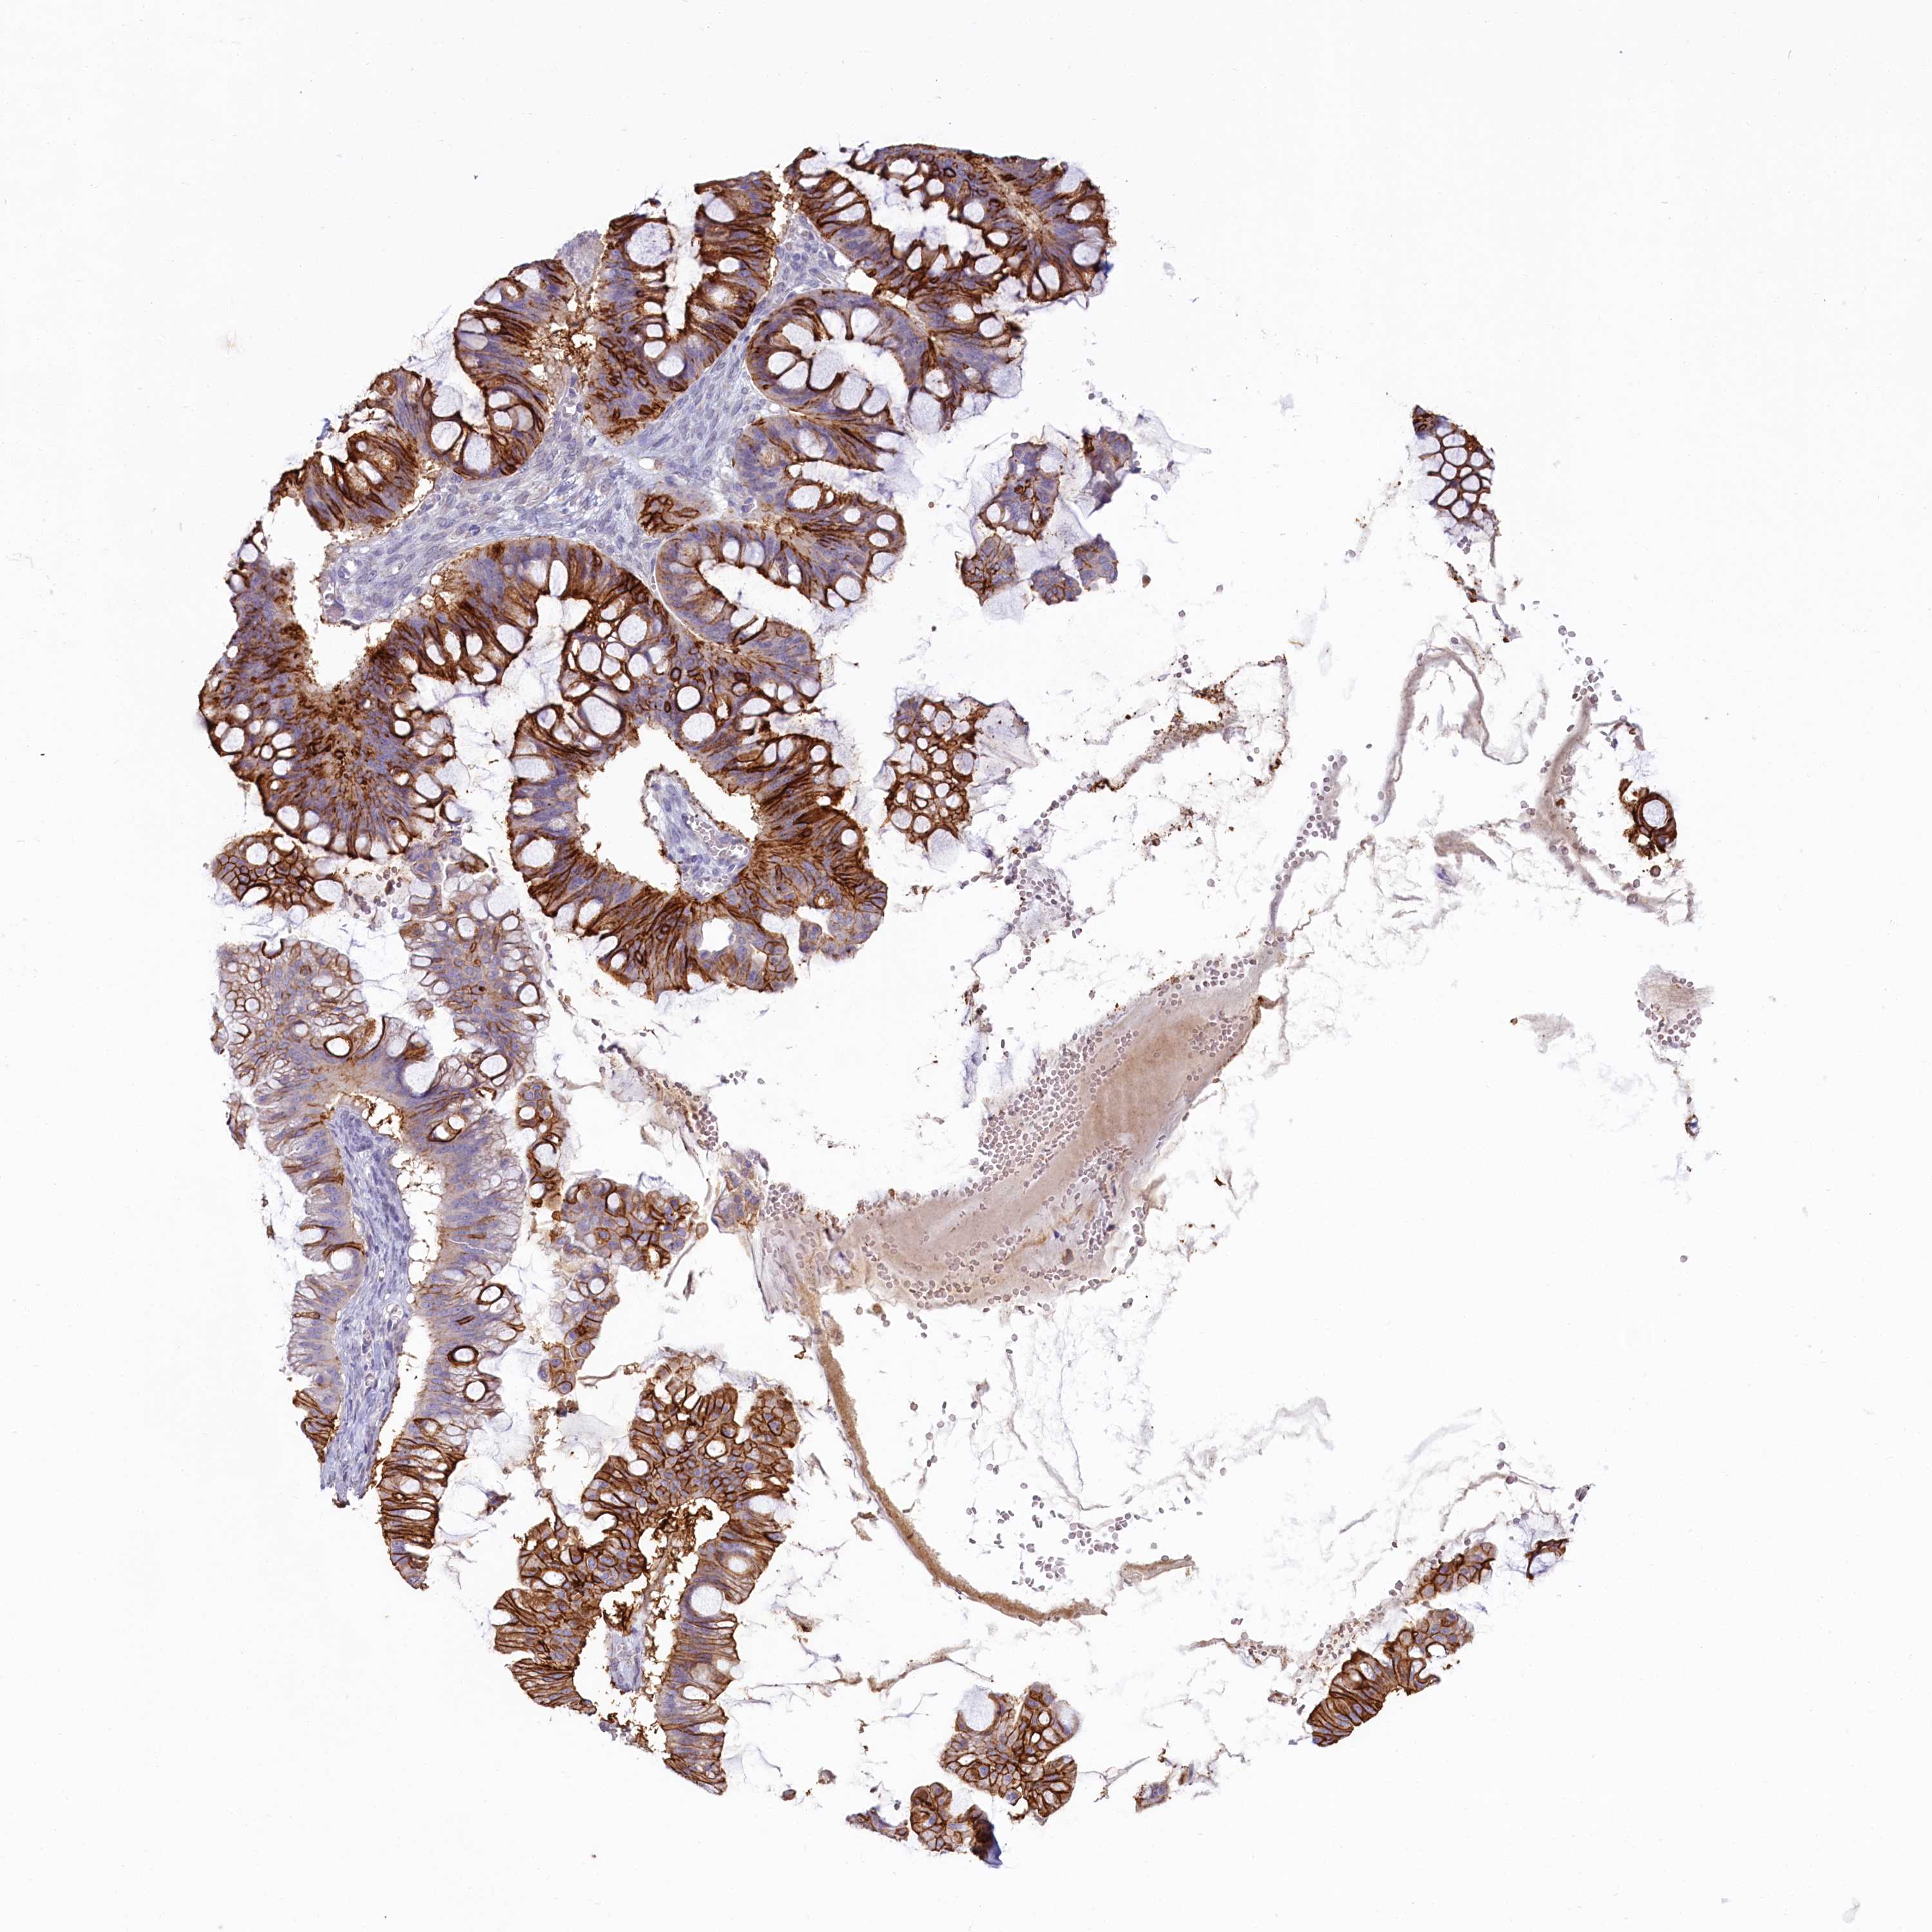

OVARIAN CANCER - Protein expressioni

A mouse-over function shows sample information and annotation data. Click on an image to view it in a full screen mode. Samples can be filtered based on level of antibody staining by selecting one or several of the following categories: high, medium, low and not detected. The assay and annotation is described here.

Note that samples used for immunohistochemistry by the Human Protein Atlas do not correspond to samples in the TCGA dataset.

Antibody stainingi

Antibody staining in the annotated cell types in the current human tissue is reported as not detected, low, medium, or high, based on conventional immunohistochemistry profiling in selected tissues. This score is based on the combination of the staining intensity and fraction of stained cells.

Each image is clickable and will lead to virtual microscopy that enables deeper exploration of all samples and also displays staining intensity scores, fraction scores and subcellular localization as well as patient and tissue information for each sample.

Antibody HPA037433

Antibody HPA037434

Cystadenocarcinoma, serous, NOS

Carcinoma, endometroid

Cystadenocarcinoma, mucinous, NOS

Carcinoma, NOS